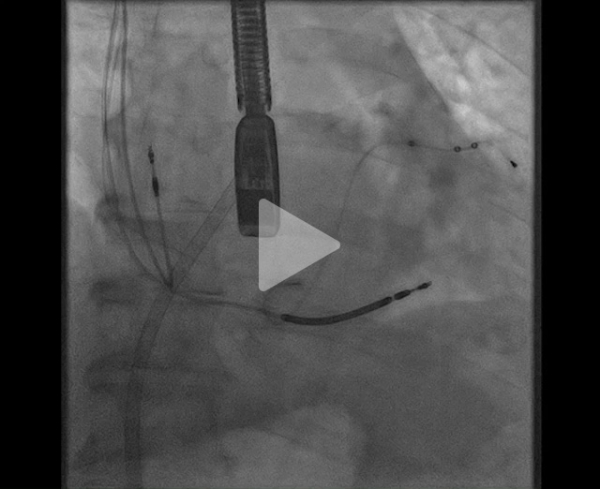

Staff pluridisciplinaire dédié : décision de tentative de traction de la sonde pour limiter le bouclage +/- guidage ETO pour réévaluer la fuite en temps réel.

En cas d'échec, explantation + réimplantation sonde VG chez ce patient dépendant de la resynchronisation (pas de gain FEVG mais dégradation de la FE et de la symptomatologie en l’absence de CRT)